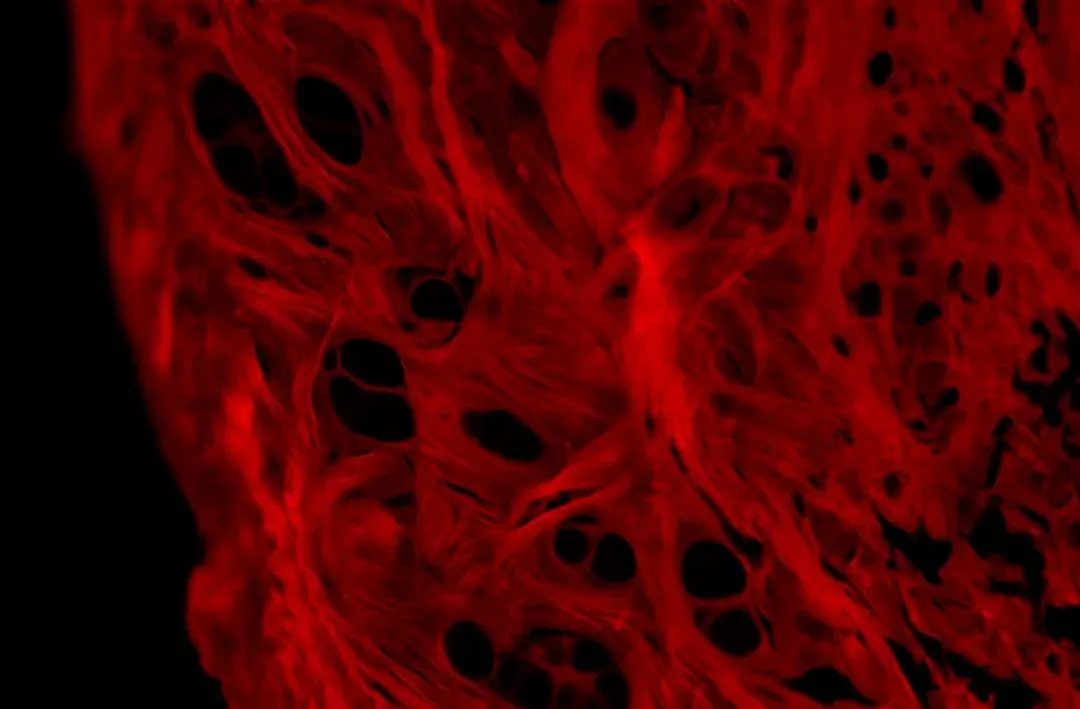

Tissue Repair: Inflammation, Scars, and Recovery

Whenever you twist an ankle, strain a muscle, or bruise your thigh, your body starts a healing script that’s surprisingly consistent across different tissues. First comes inflammation, with swelling, warmth, and sometimes pain, which is your body’s version of sending an emergency crew to the scene. Then comes the repair phase, when cells rebuild damaged structures and lay down fresh collagen, followed by a longer remodeling phase, where that new tissue is shaped and strengthened.

Sometimes, this repair process leaves behind scars, especially when the damage is deep or repetitive. A scar is your body’s way of patching a hole quickly, even if the patch is not a perfect match to the original. Over time, scars can fade, soften, and become less noticeable, but they rarely vanish entirely. They’re like physical reminders that healing happened, even if it wasn’t flawless.